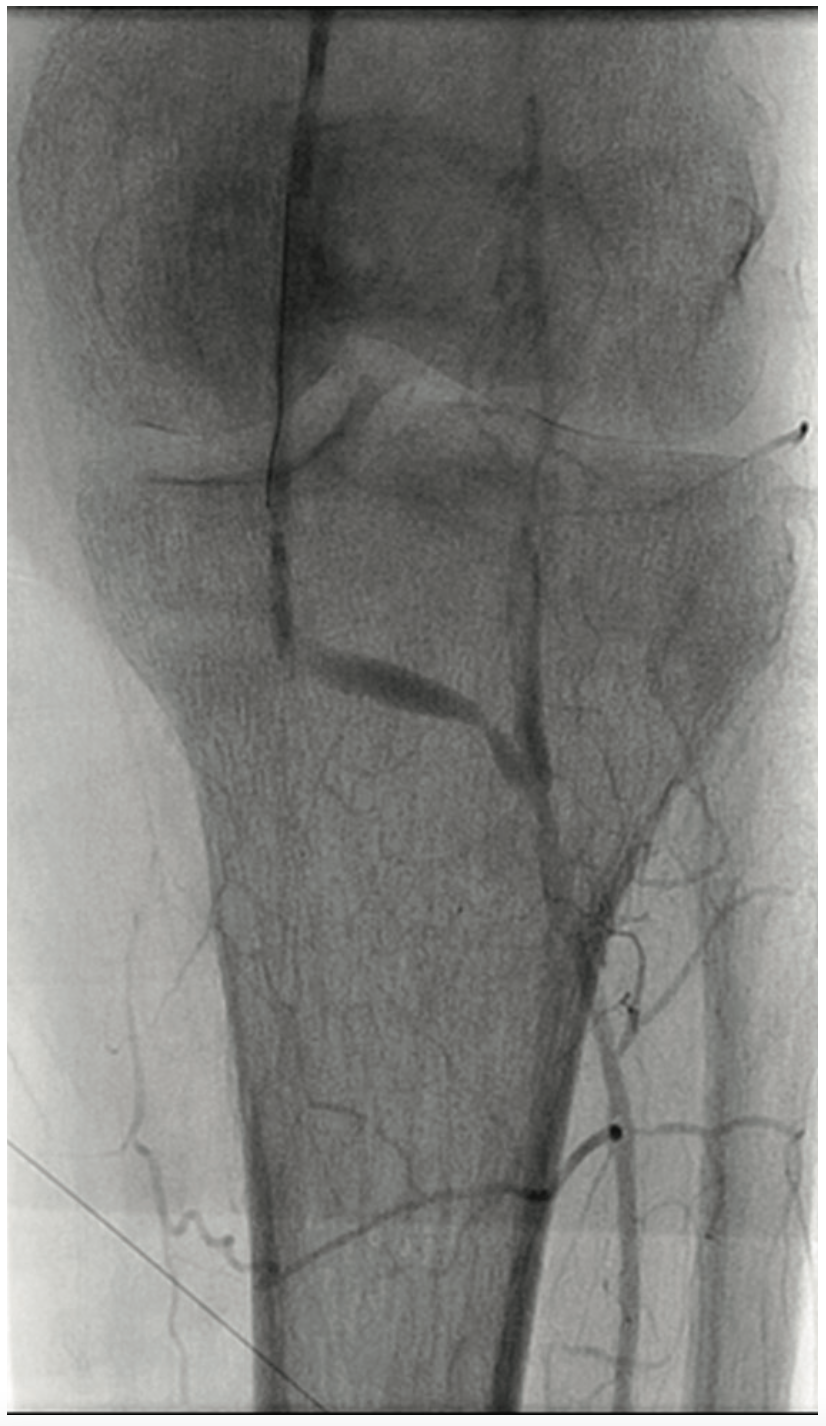

A 63-year-old male smoker presented with critical limb ischemia of his left foot. Four years prior, the patient underwent right fem-pop bypass after failed intervention on his right leg. He ended up losing the fifth digit on his right foot. Three years prior to his visit, he underwent a fem-pop bypass procedure on his left leg for severe claudication after failed intervention. One year later, he underwent a redo fem-pop on his left leg with a cadaveric vein. Twelve months prior to the visit, a self-expanding stent was placed in that fem-pop graft because of continued foot ischemia. Seven months prior to his visit, his symptoms re-occurred, and the patient was told nothing could be done after an angiogram showed the vessel was occluded. The patient suffered from polyneuropathy and was unable to walk, but did not want amputation. The patient was on cilastazol and coumadin, and had type II diabetes mellitus. His exam revealed a cool and red left foot, but no ulcers. Capillary filling was adequate. The right dorsalis pedis was normal, and there was no popliteal pulse on either side and no left pedal pulses. A contralateral approach was utilized and revealed the graft was occluded on the left side (Figure 1). The patient likely had thrombus in the graft, and we felt that a laser would be appropriate, used either in the traditional manner or with the step-by-step method. Whenever the step-by-step method is utilized, we use the CrossLock LP device (Radius Medical) for centering (Figure 2). The CrossLock LP is usually utilized for infrapopliteal lesions, but in this case, the 3 mm elastomeric balloon would fit well into the nub of the bypass graft. We immediately subtended the bypass graft all the way down and then were able to access the infrapopliteal vessels (Figures 3-4). We performed .9 mm laser (Spectranetics) in the graft and balloon angioplasty (Figure 5). Two Xience stents (Abbott Vascular) were placed, a 4.0 cm and 3.5 cm, at the anastomosis site, and because of residual stenosis at the popliteal, we placed a 5.5 cm Supera stent (Abbott Vascular). Due to multiple failures of the graft, the graft was covered with a 6.0 mm x 250 mm Gore Viabahn stent graft (W.L. Gore & Associates). At the end of the procedure, we were able to achieve brisk 2-vessel runoff (Figures 6-7). Fluoroscopic time was long at 73 minutes and the contrast utilization was 236 mL.